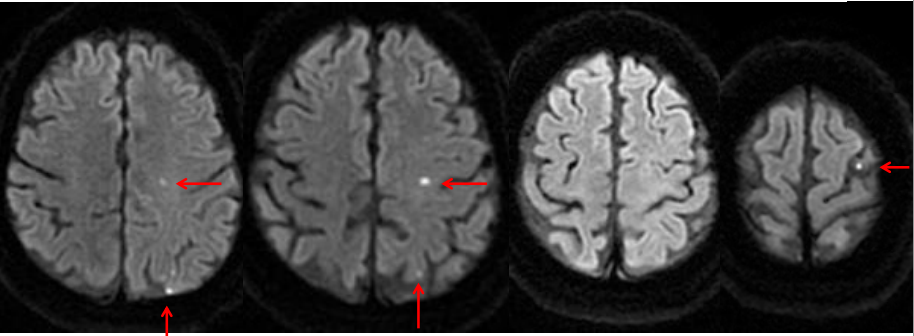

A 45 y/o woman with hypertension is resuscitated after a cardiac arrest. On day three she is able to move her face, hands, and feet, but is unable to move her limbs. A T2W1 MRI is taken at this time and is attached.

What is the general pathogenesis behind her symptoms and the MRI findings?

Hypotension secondary to cardiac arrest caused ischemia within the cerebrum, which has damaged her primary motor cortex bilaterally.

What cellular change is causing the bright vertical bands in each hemisphere?

Cytotoxic edema secondary to ischemia. The ischemia disrupts metabolism, which shuts down the Na+/K+/ATPase and causes cellular retention of Na+ and water.

Recall that on a T2W1 MRI, fluid (including water and CSF) is bright (as well as fat).

Why is the cellular change visaulized by the MRI localized to vertical bands?

This injury is a watershed infarction between the areas perfused by the ACA and MCA. The MCA area of the brain is especially susceptible to ischemia, and so its watershed area with the ACA will be the first to suffer. The bright vertical bands show cellular injury in the watershed zones across the entire cerebrum.

Where is ACA-MCA watershed area in this picture?